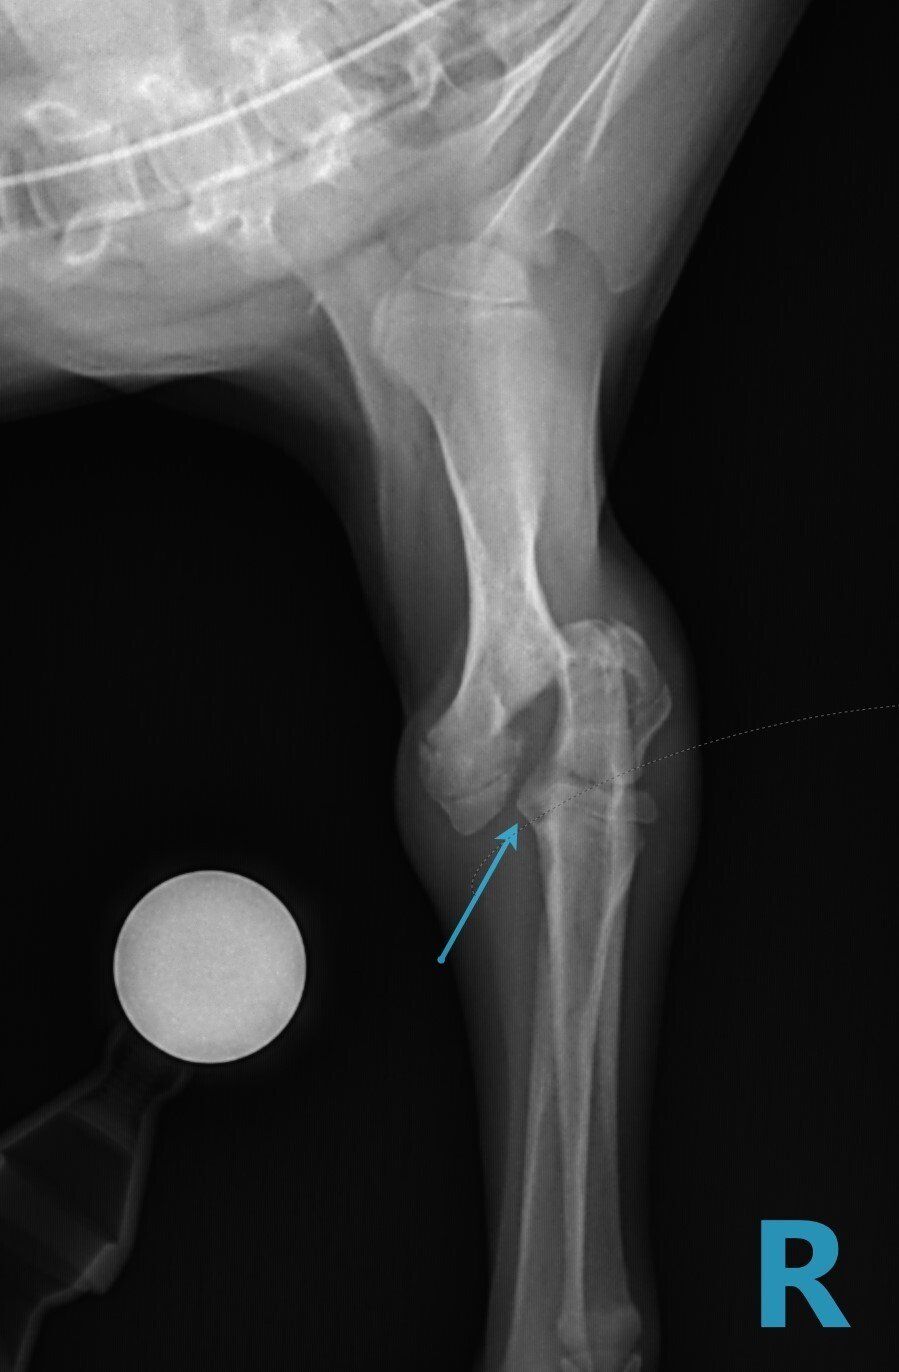

Leg fractures are one of the most common orthopedic problems presented at our clinic and usually result from a traumatic mishap. They can be treated in a variety of ways depending on the location and type of fracture. We can apply a cast to treat certain fractures; however, many fractures will require surgical intervention:

- “Pinning” stabilizes the fracture by inserting a long stainless steel rod into the middle of the bone across the fractured area.

- “Plating” involves attaching a flat stainless steel plate to the bone using screws on either side of the fracture.

Below are x-rays of just a few orthopedic surgeries before and after that Dr. Gose has performed.